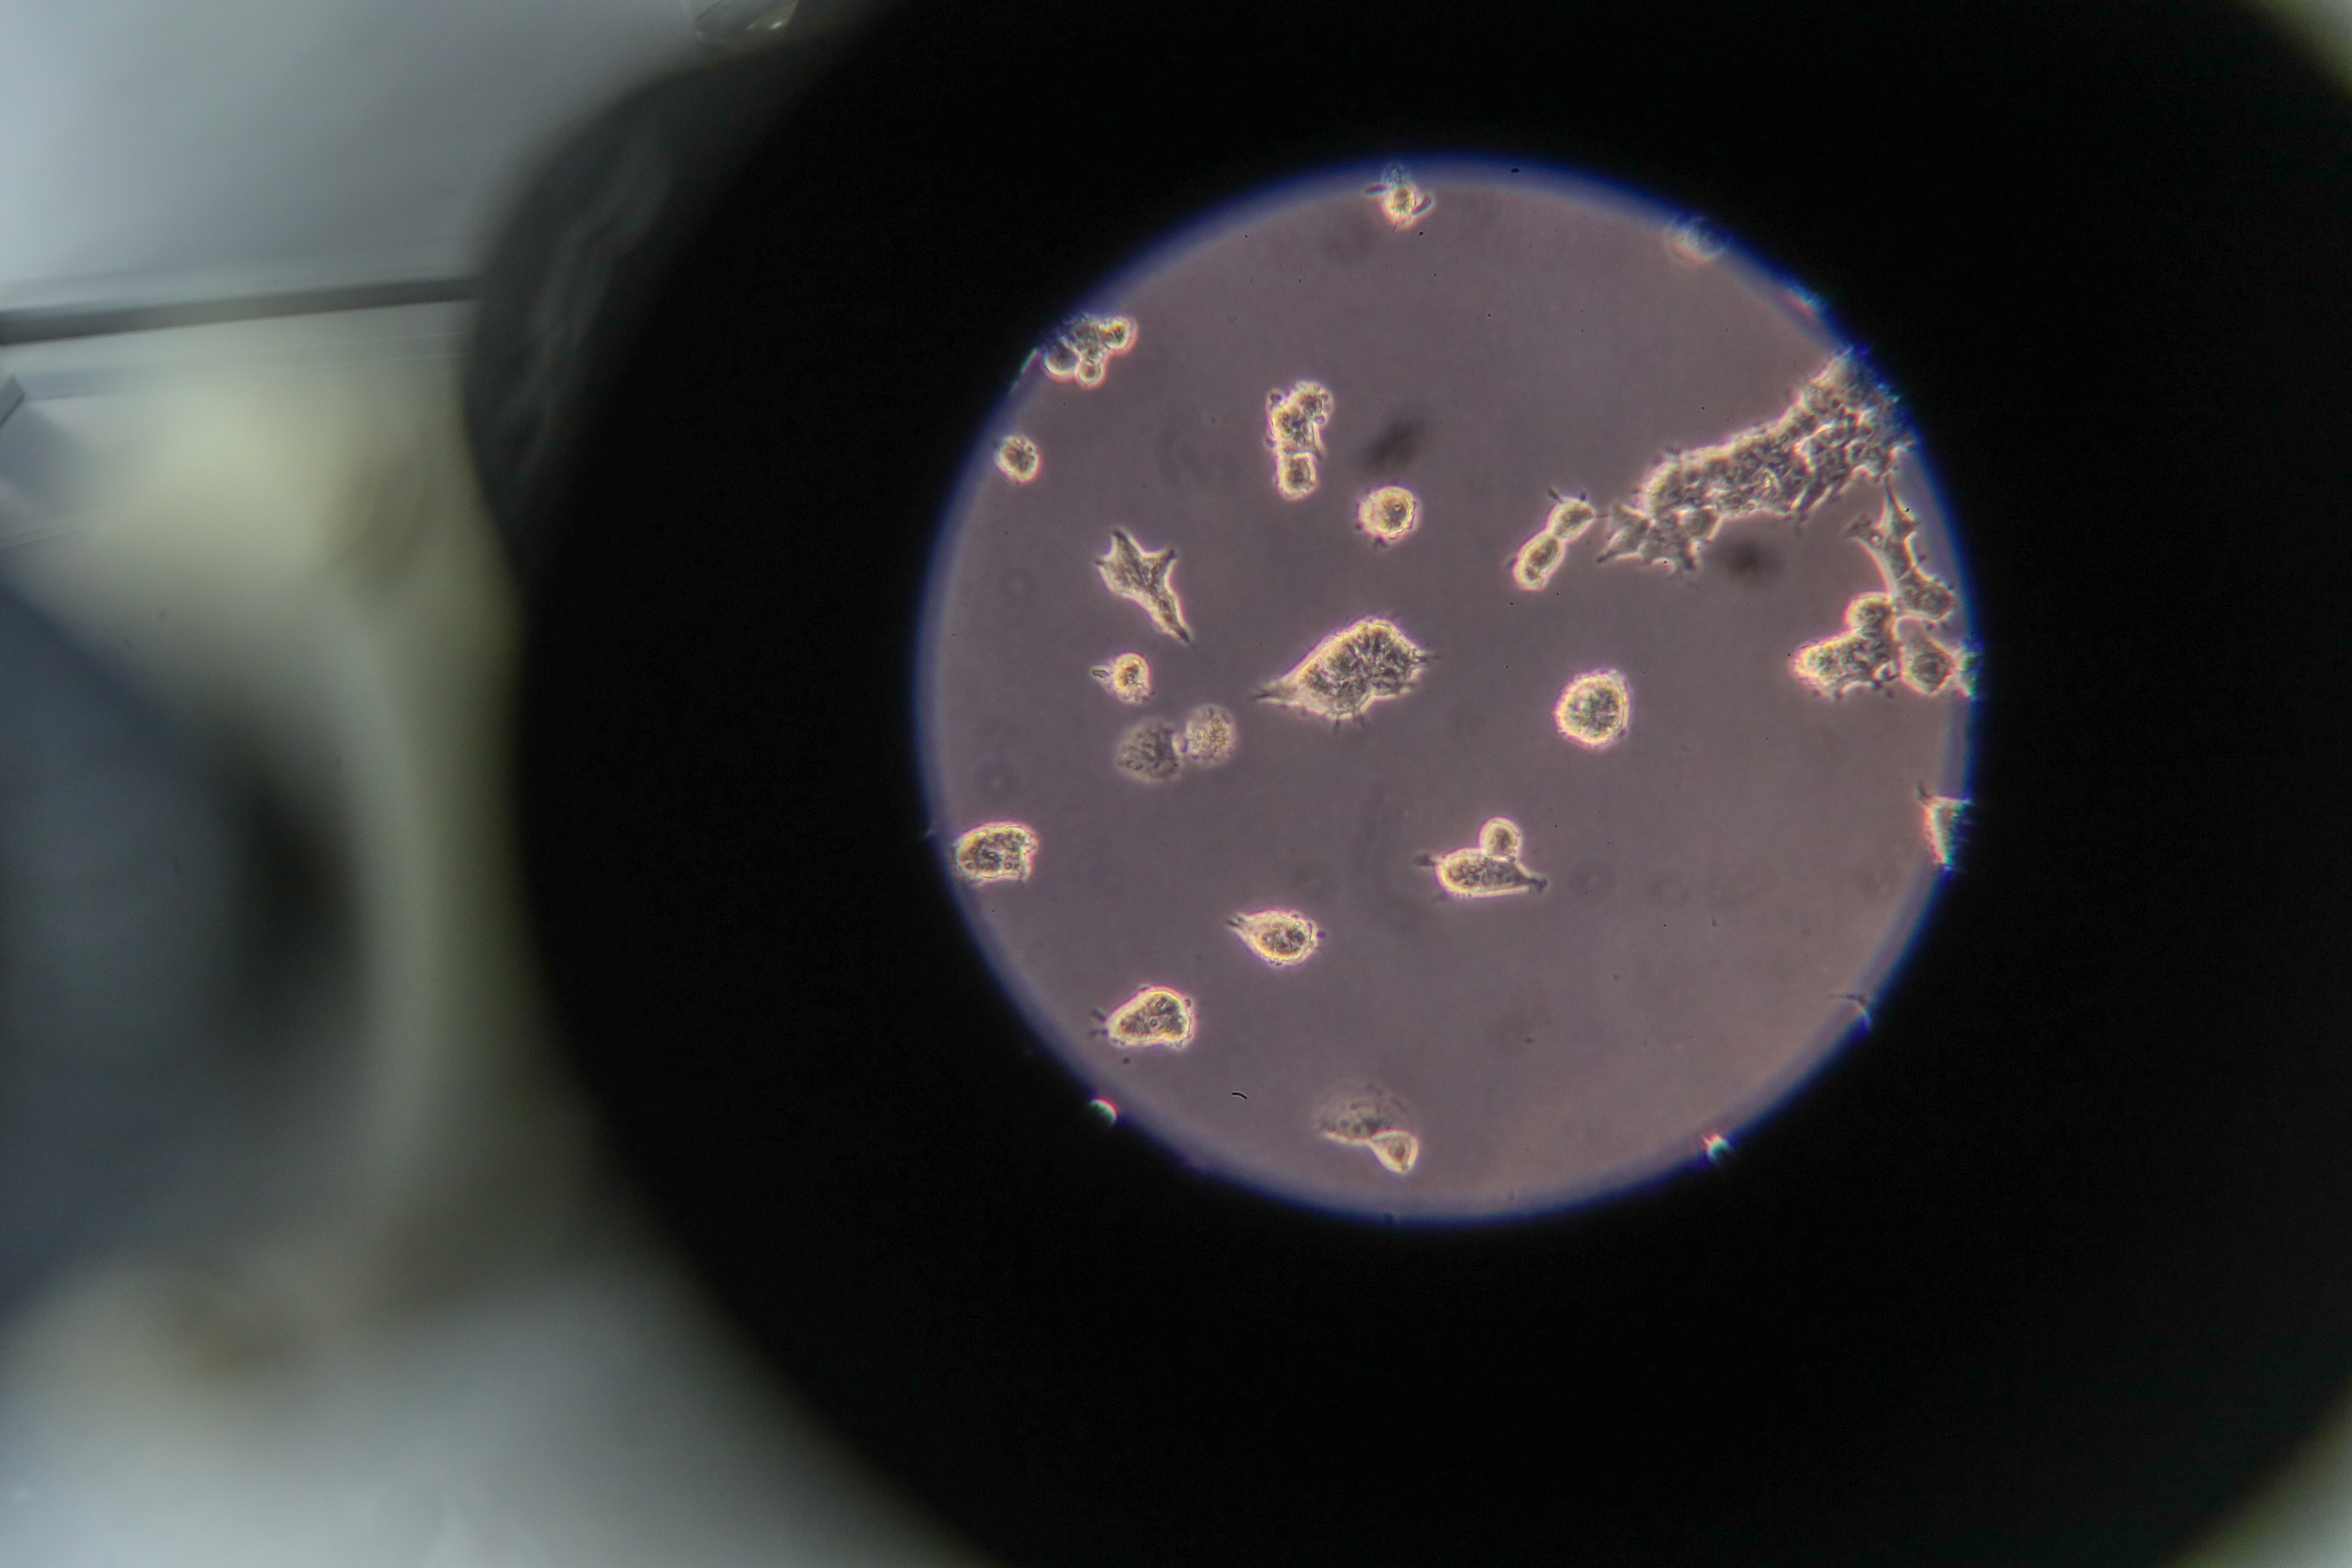

The Center has developed its own dead whole-virion vaccine against the novel coronavirus infection. The vaccine is currently subject to clinical test.

Whole-virion vaccines are based either on artificially weakened viruses incapable of causing a disease or killed (inactivated) viruses.